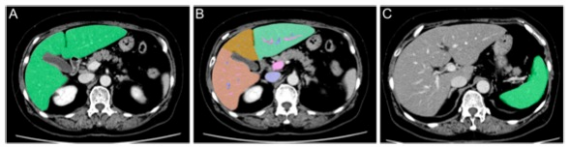

圖 一位患有肝癌的67歲婦女的CT圖像。A TLV的軸位圖像。原始數據被手動發送到工作站后,TLV實現自動測量。B 分割的TLV軸位圖像。鐮刀狀韌帶和中央肝靜脈被用作標志,分別從內側和外側分離出II、III和IV。C SV的軸位圖像。在這個工作站(ver5.5)中,SV是手動測量的